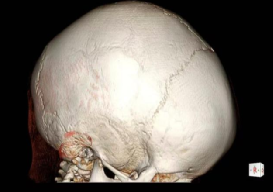

接诊后,医疗团队为凯凯进行了详尽的检查。入院查体显示,凯凯头围50厘米,头颅外观呈现特征性的前后径较长,前额部隆起,触诊可及矢状缝、冠状缝及颞鳞缝区域骨质硬化,失去了正常婴儿颅缝应有的弹性与间隙。结合外院头颅CT三维重建结果——清晰显示冠状缝、矢状缝、颞鳞缝过早闭合,并伴有额骨前突——诊断明确:多颅缝早闭,亦即狭颅症。

术前